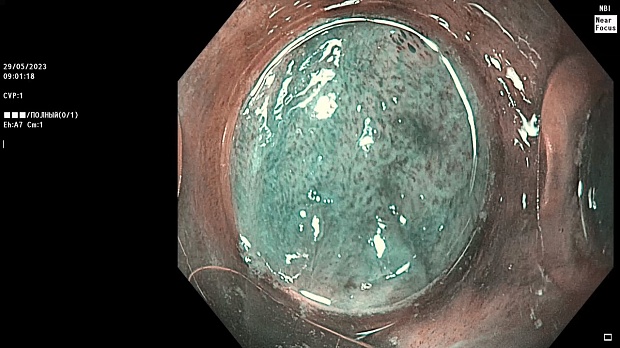

Иллюстрация №1: Эндофото. Сидероз нижней трети пищевода, осмотр в белом свете

Согласно полученным данным - в среднегрудном и нижнегрудном отделах пищевода определялась проксимальная граница плоских неправильной формы поверхностных рубцов суммарной протяженностью до 8,0 см. На этом фоне в зонах поверхностных рубцов по задней полуокружности визуализировались участки гиперпигментации в темный цвет (Рис. 1). При исследовании в режиме Dual Focus было отмечено наличие мелких (до 0,001 см) черно-коричневых включений, расположенных субэпителиально - в строме слизистой оболочки, сливания их в единый конгломерат не определялось (Рис. 2). При эндосонографии с применением минидатчика с частотой сканирования 20МГц выявлено, что все слои стенки четко дифференцируются, не утолщены, в слизистой оболочки визуализированы мелких гиперэхогенные включения с эхотенями (Рис. 3).

Протокол ЭГДС

В пищеводе в шейном его отделе на уровне 16 см от резцов циркулярно визуализированы единичные синюшные флебоэктазии размерами до 0.5 см. Дистальнее пищевод визуально не изменен до уровня 28 см от резцов, где определяется проксимальная граница плоских неправильной формы поверхностных рубцов, распространяющихся до уровня 36 см от резцов. На этом фоне в зонах поверхностных рубцов по задней полуокружности визуализированы участки гиперпигментации в черно-коричнеый цвет. При осмотре в режиме Near Focus с увеличением - между зон пигментации определяются расширенные капилляры типа II по Inoue-классификации. При биопсии отмечена десквамация плоского эпителия, визуализированы мелкие черно-коричневые включения в строме слизистой оболочки, размеры их до 0,001 см, сливания их в единый конгломерат не отмечается. При эндосонографии с датчиком 20Мгц в исследуемой зоне в слизистой оболочке определяются гиперэхогенные включения, в то время как в подслизистом слое - зоны со сниженной эхогенностью. При биопсии отмечается уплотнение ткани, однако истинной фрагментации не определяется. Уровень Z-линии совпадает с уровнем анатомического кардиоэзофагеального перехода. Розетка кардии эластичная, смыкается не полностью, расположена на уровне пищеводного отверстия диафрагмы.